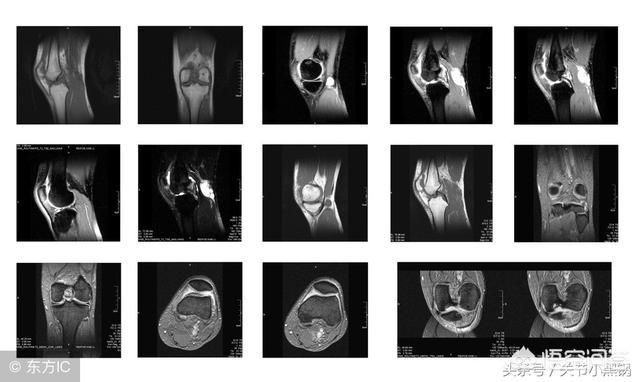

(3) 核磁気共鳴検査

また、MRIは軟部組織の解像度が高く、放射線を使用しないため、費用の割に優れた検査であり、骨、脳、筋肉、肝臓、胆嚢の疾患の診断に非常に明確な利点がある。MRIは高価でもあり、1部位で1,000円以上、特殊な造影剤を使用すればさらに高額になる。

2.磁気共鳴(MRI)検査はあまり一般的ではない!

患者に外傷歴がある場合、あるいは関節靭帯の断裂や半月板損傷などが疑われる場合、医師は患者に磁気共鳴画像法(MRI)を受けるよう勧める。MRIは腫瘍などの除外にも使用できる。また、通常のX線検査よりもはるかに高額で、スキャニングMRIは850ドル++、エンハンストMRIは1400ドル++、X線検査は120ドル++程度である。

2.磁気共鳴検査(MR)

MRIは体の一部分で数百ドルかかり、広東省では700-800ドルで、地域によって値段が違う。価格は病院ではなく、地方価格局が決める。1部位の掃引+強化なら1000円以上かかる。複数の部位の場合、価格は重ね合わされ、いくつかの機能配列も別途請求される。